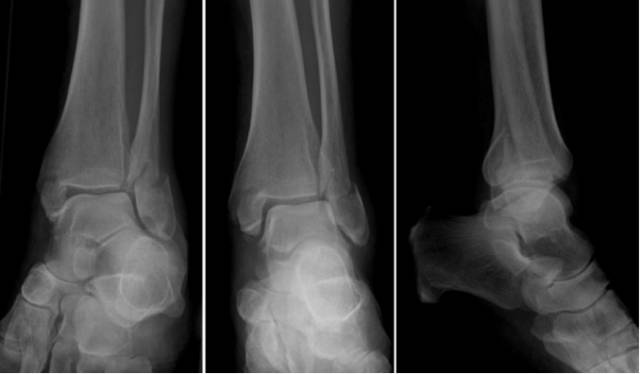

Pilon骨折

是指胫骨远端关节内骨折,常常由垂直暴力所致,常常合并腓骨骨折和严重的软组织损伤。